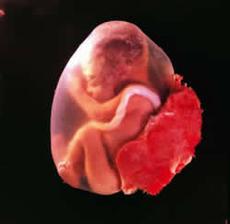

Vajíčko ve vejcovodu čeká zhruba 12 až 24 hodin na příchod spermií. V ejakulátu je v průměru 250 milionů spermií, z toho pouze zhruba 400 se dostane až k vajíčku ve vejcovodu, přičemž cesta z pochvy do vejcovodu trvá spermiím až 10 hodin. Obvykle pouze jedna spermie uspěje a pronikne po zhruba 20 minutách snahy do vajíčka. Tím dojde ke vzniku oplodněného vajíčka, tzv. zygoty. V příštích 10 až 30 hodinách dochází ke splynutí genetických informací vajíčka a spermie. Pohlaví dítěte je určeno již v této chvíli – pokud spermie nese chromozom Y, narodí se chlapec, pokud chromozom X, narodí se dívka.

zázrak lidské života na videu